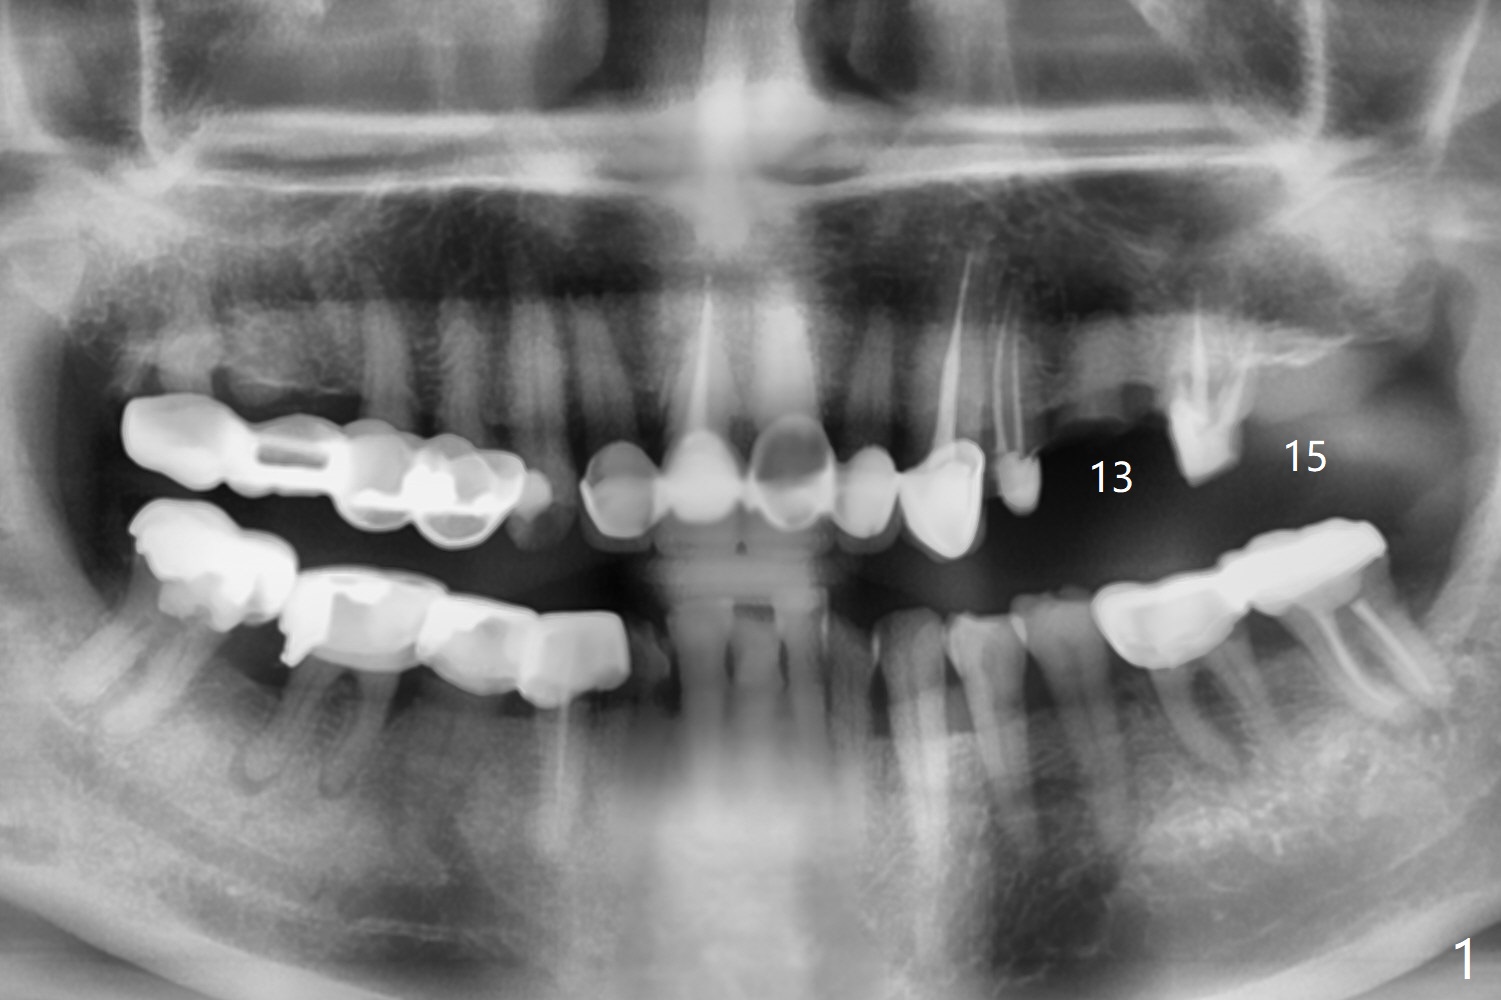

A 74-year-old man with multiple crowns and FPD needs implants at #13 and 15 (Fig.1). To avoid drills or implant (particularly immediate one) touching the neighboring root, 2.2 mm drill will reach the depth (sequentially) first and take segmental panoramic X-ray. Then return to the original sequence: diameter first and depth second to avoid bone necrosis.